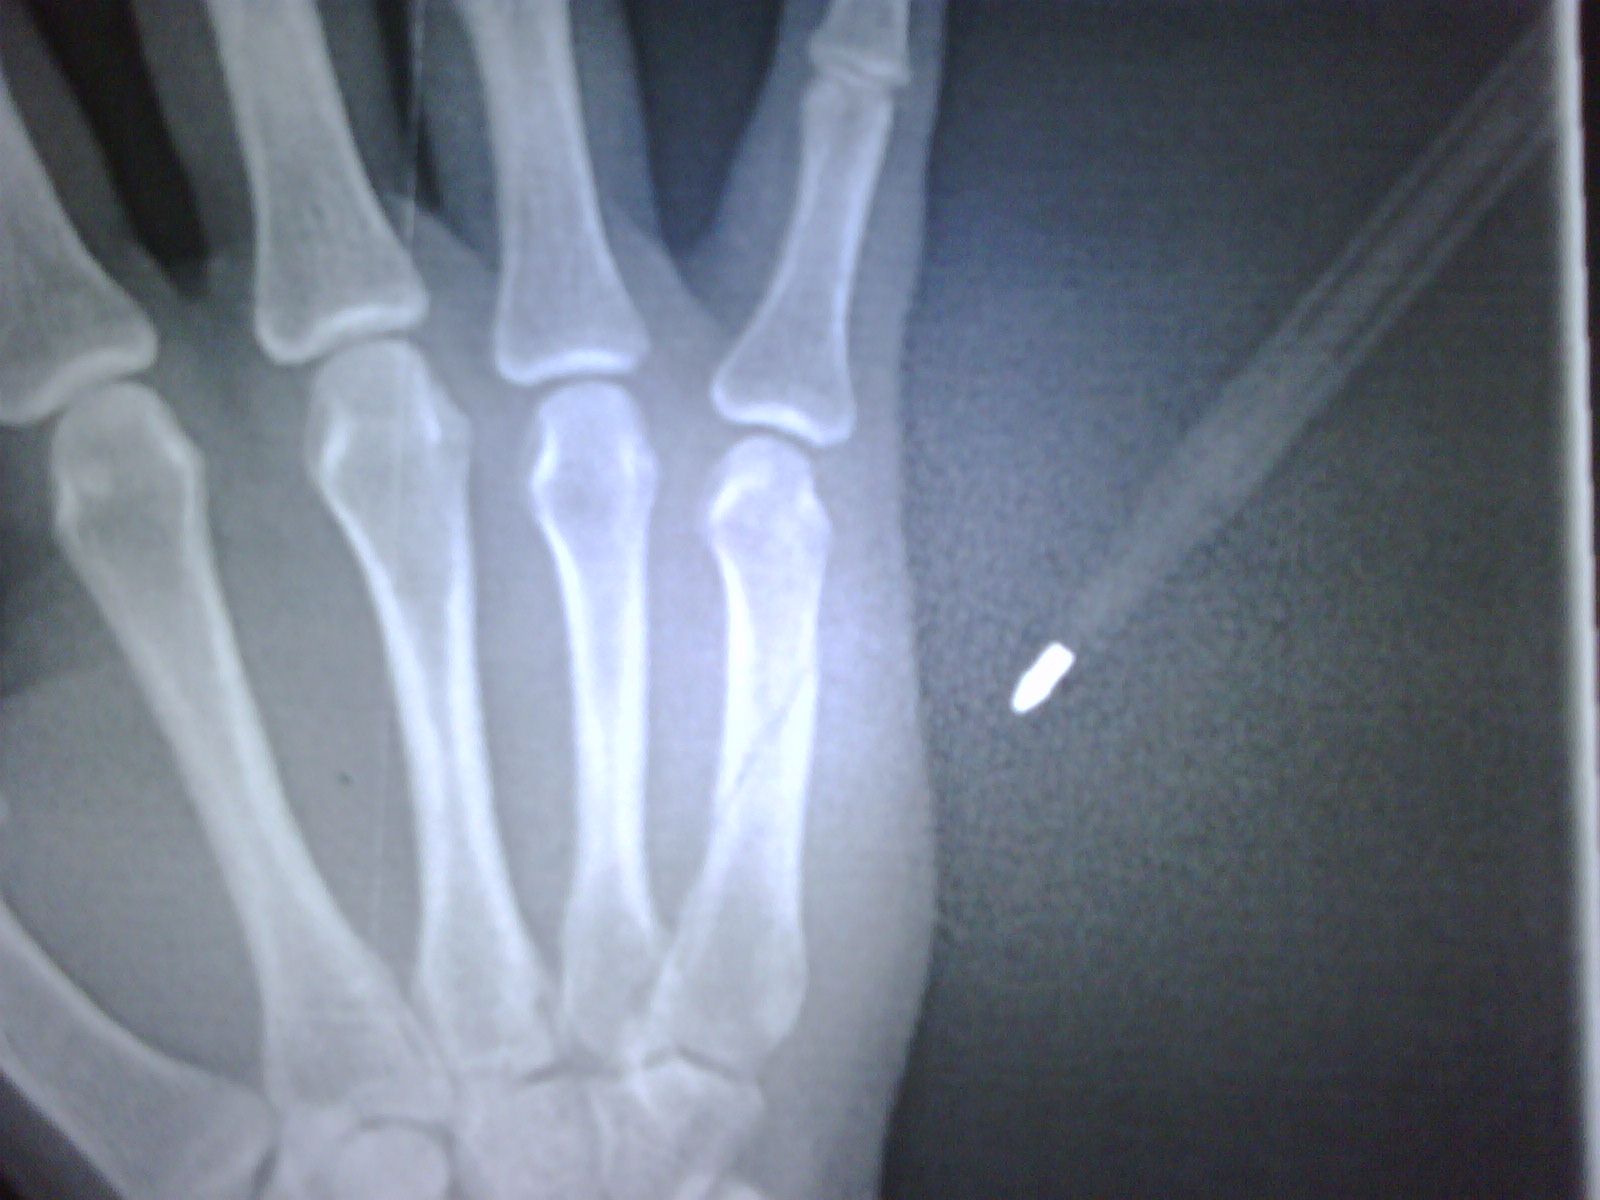

HAND BROKEN